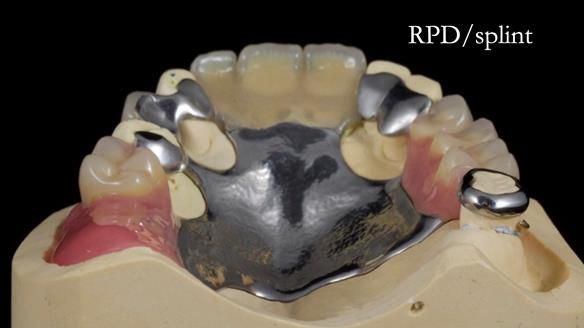

This edition features the case of Edgar, who sought help for a poorly fitting, acrylic-based partial denture that rocked, affected his speech, and caused discomfort. After considering various treatment options, including dental implants, Edgar opted for a metal-based removable partial denture, designed by myself with input from my technician, Rowan Garstang.

Treatment Process: I provided the clinical work while Rowan Garstang delivered the technical aspects. The treatment required fifteen visits to fit and review Edgar.